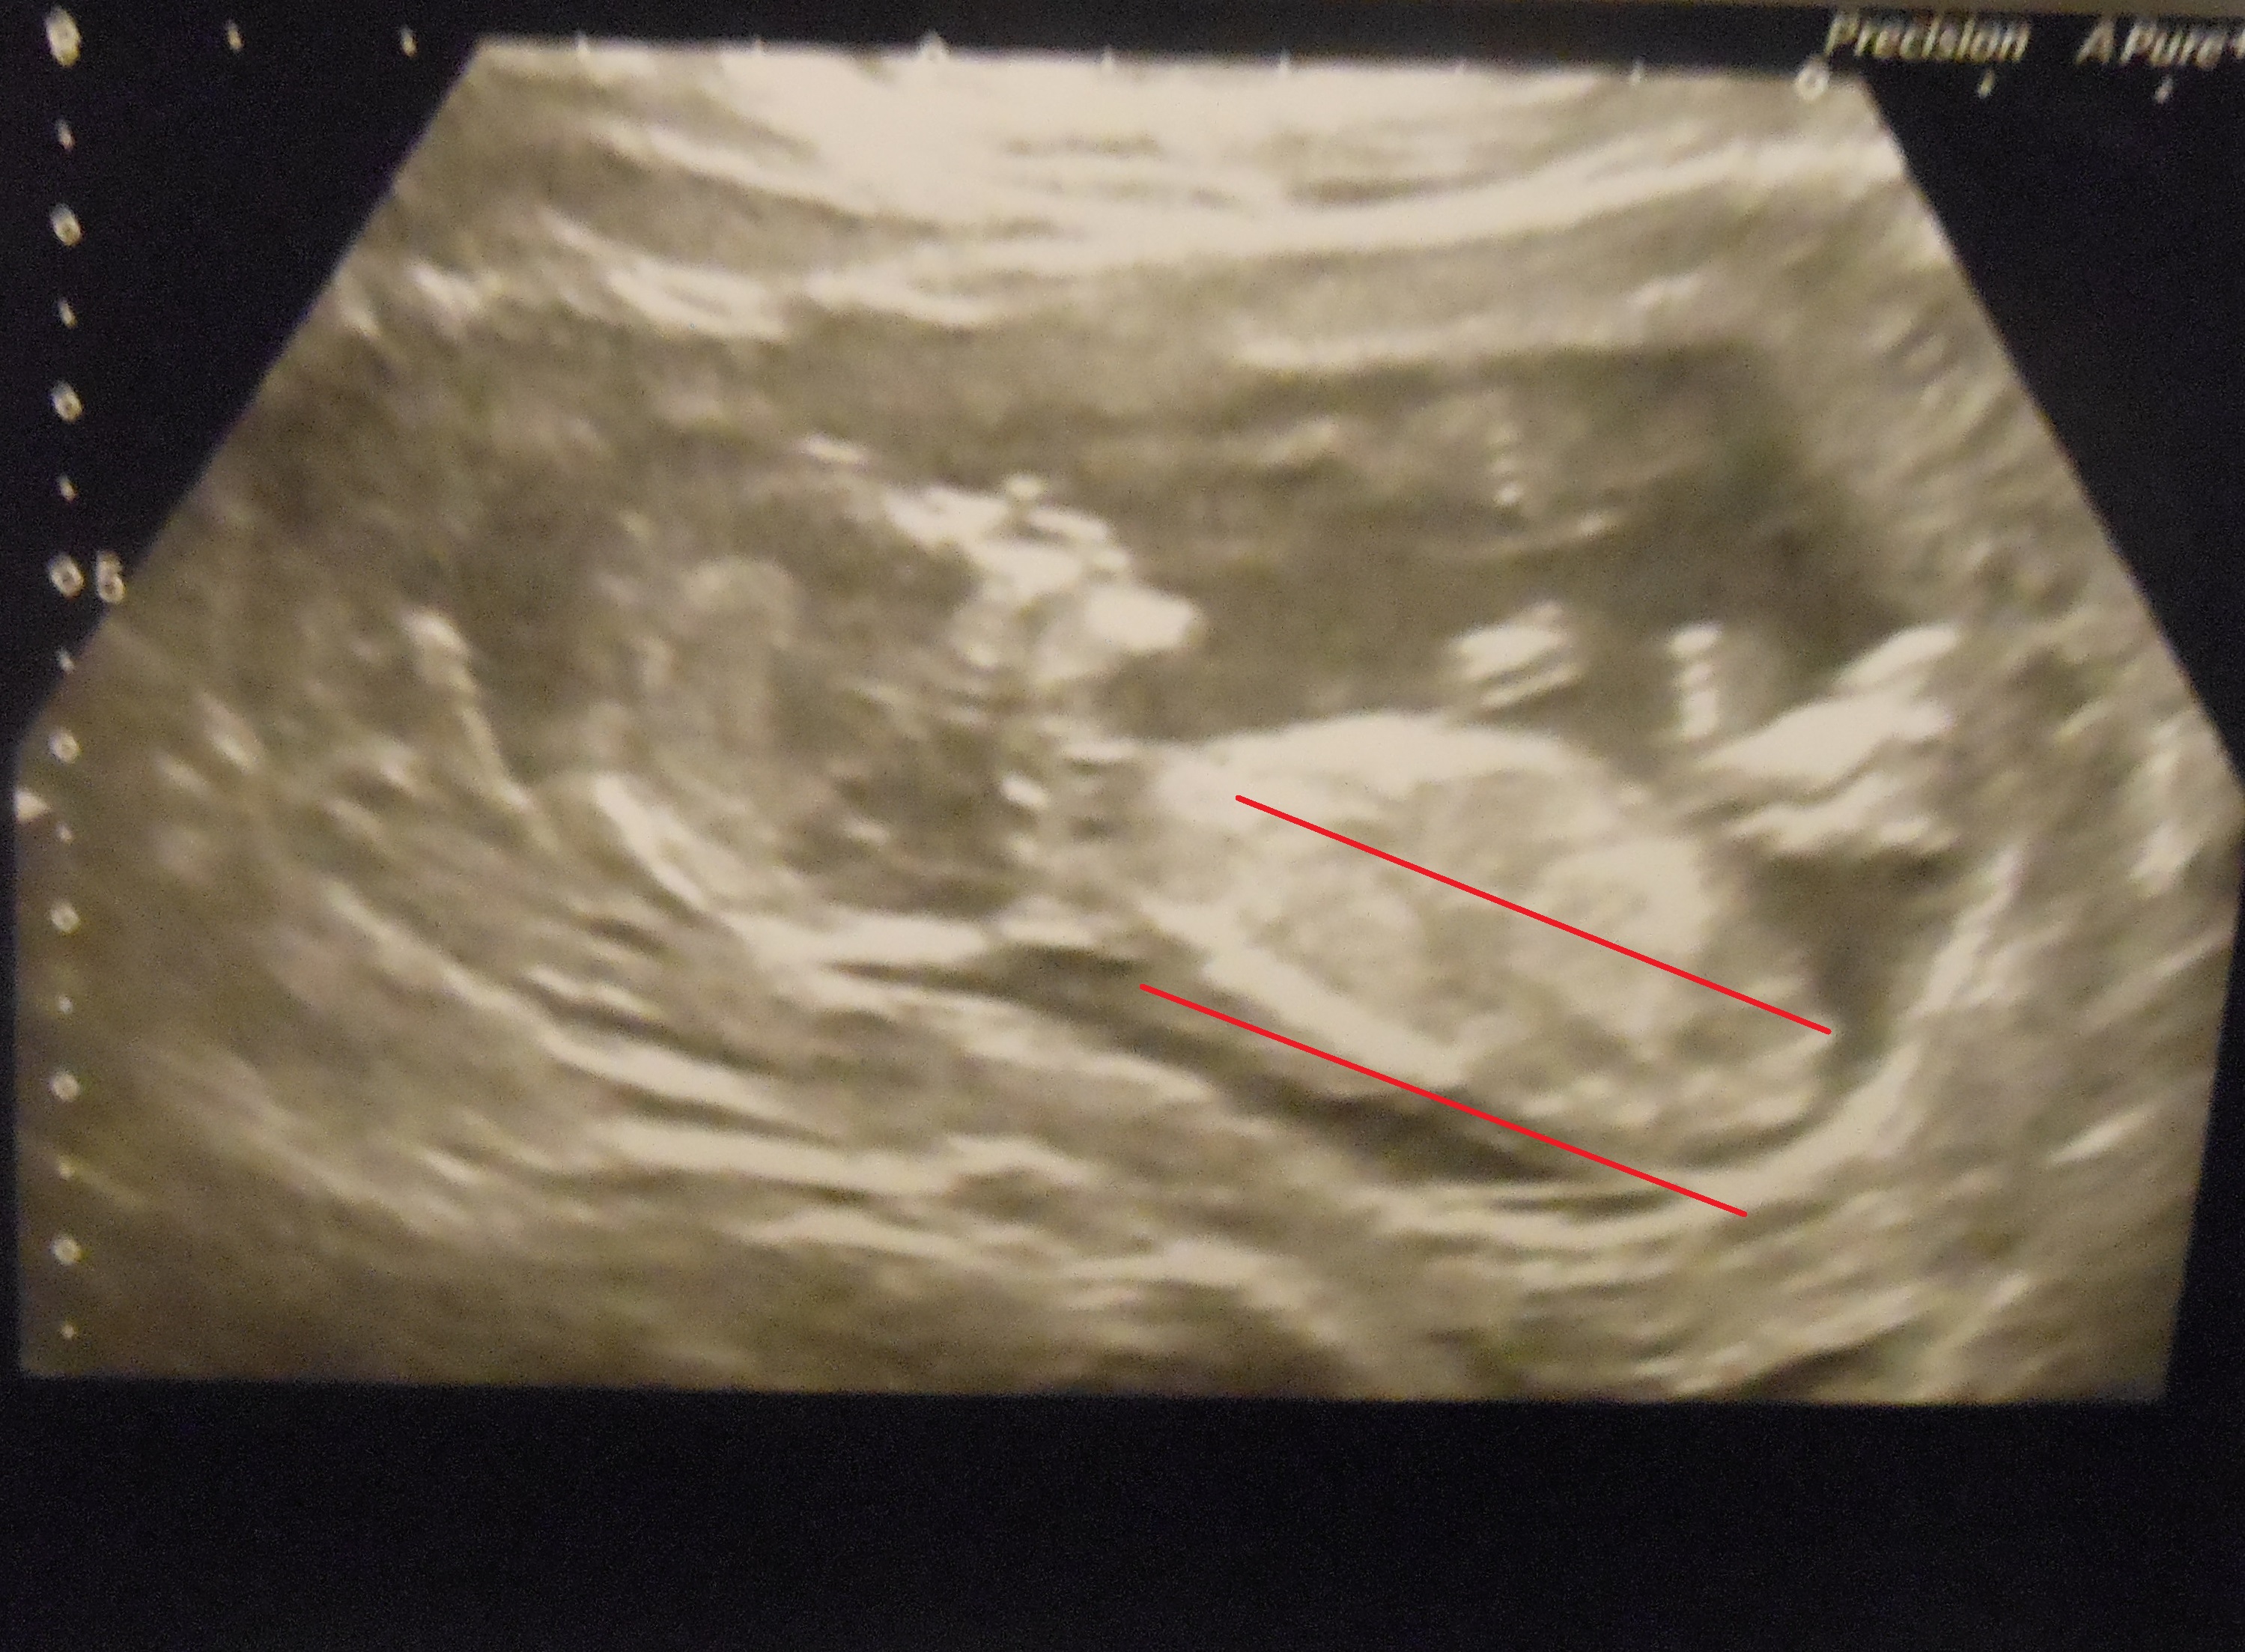

I can't work out which is the right way to look at the nub. This was taken when baby was 13 weeks + 4. My SIL thinks it looks like a girl (so did I originally) and says she has rarely been wrong and guessed her babies and her friends correctly. However when I posted on my birthclub on baby centre all replies said boy! I just want to know what you guys think and what your opinion is as it's totally driving me mad. Any expert eyes and replies are greatly appreciated :)

Attachment 23778Attachment 23779Attachment 23780